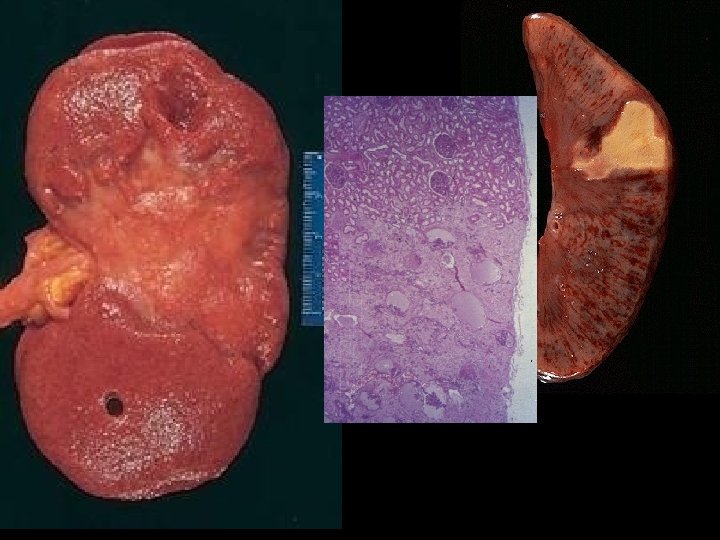

PATHOLOGY • • MULTIPLE ORGAN FAILURE SUBENDOCARDIAL HEMORRHAGE (why? ) ACUTE TUBULAR NECROSIS (why? ) DAD (Diffuse Alveolar Damage, lung) (why? ) GI MUCOSAL HEMORRHAGES (why? ) LIVER NECROSIS (why? ) DIC (why? )

ATN

DIC